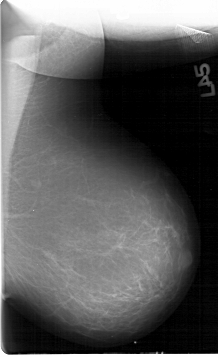

D_4200_1.RIGHT_MLO

D_4200_1.LEFT_MLO

D_4200_1.RIGHT_CC

D_4200_1.LEFT_CC

DATE_OF_STUDY 7 12 1992

PATIENT_AGE 48

DENSITY 2

LEFT_CC LINES 5326 PIXELS_PER_LINE 3886 BITS_PER_PIXEL 12 RESOLUTION 43.5 NON_OVERLAY

LEFT_MLO LINES 6781 PIXELS_PER_LINE 4126 BITS_PER_PIXEL 12 RESOLUTION 43.5 NON_OVERLAY

RIGHT_CC LINES 5311 PIXELS_PER_LINE 3901 BITS_PER_PIXEL 12 RESOLUTION 43.5 OVERLAY

RIGHT_MLO LINES 6736 PIXELS_PER_LINE 4411 BITS_PER_PIXEL 12 RESOLUTION 43.5 OVERLAY

FILE: D_4200_1.RIGHT_MLO.OVERLAY

LESION_TYPE CALCIFICATION TYPE PLEOMORPHIC DISTRIBUTION CLUSTERED

ASSESSMENT 0

SUBTLETY 2

PATHOLOGY MALIGNANT